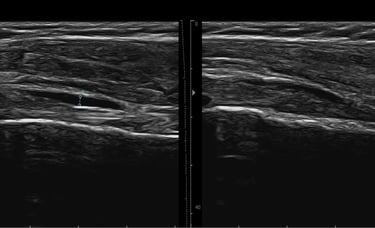

Permette di osservare in tempo reale i tessuti durante il movimento. In questo modo posso analizzare il comportamento muscolare, la qualità del gesto e la risposta dei tessuti a un esercizio. È uno strumento utile per comprendere meglio come ti muovi, personalizzare il trattamento e monitorare i cambiamenti nelle sedute successive

Metodo RUSI

Il metodo RUSI trasforma l’ecografia da semplice strumento diagnostico a partner attivo nella riabilitazione, permettendo di vedere, capire e correggere ciò che accade nel corpo mentre si muove